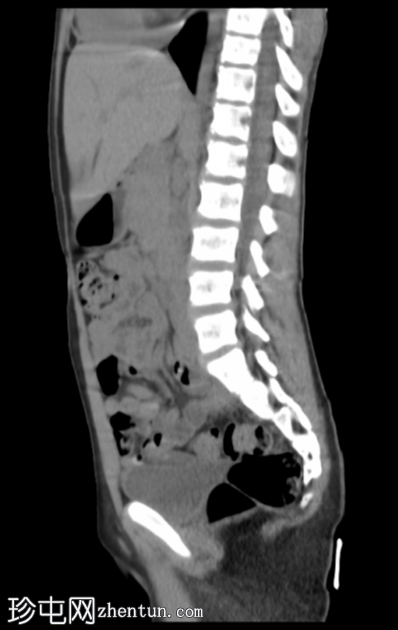

矢状位

平扫

腹部和盆腔CT扫描结果正常。

泌尿系统正常。未见尿路结石或反流压改变。

本病例显示一名10岁男孩的腹部、盆腔和泌尿系统CT扫描结果正常。